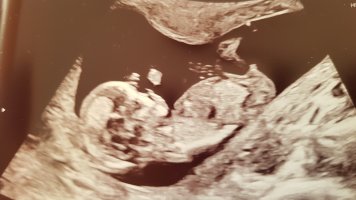

Hurra!Det må kanskje ha vært den bakerste som er nub, for dette viste seg på OUL å være en guttja. ganske sikker på at dette er nub og at dette er en jente. barnet sitter nesten, men vinkelen er helt flat. det ville vært godt synelig 13+5 hvis det var en gutt.

Måtte tilbake å se nå, det er så gøy å få vite om det var riktig eller ikke, så lærer man litt underveisDet må kanskje ha vært den bakerste som er nub, for dette viste seg på OUL å være en gutt![]()